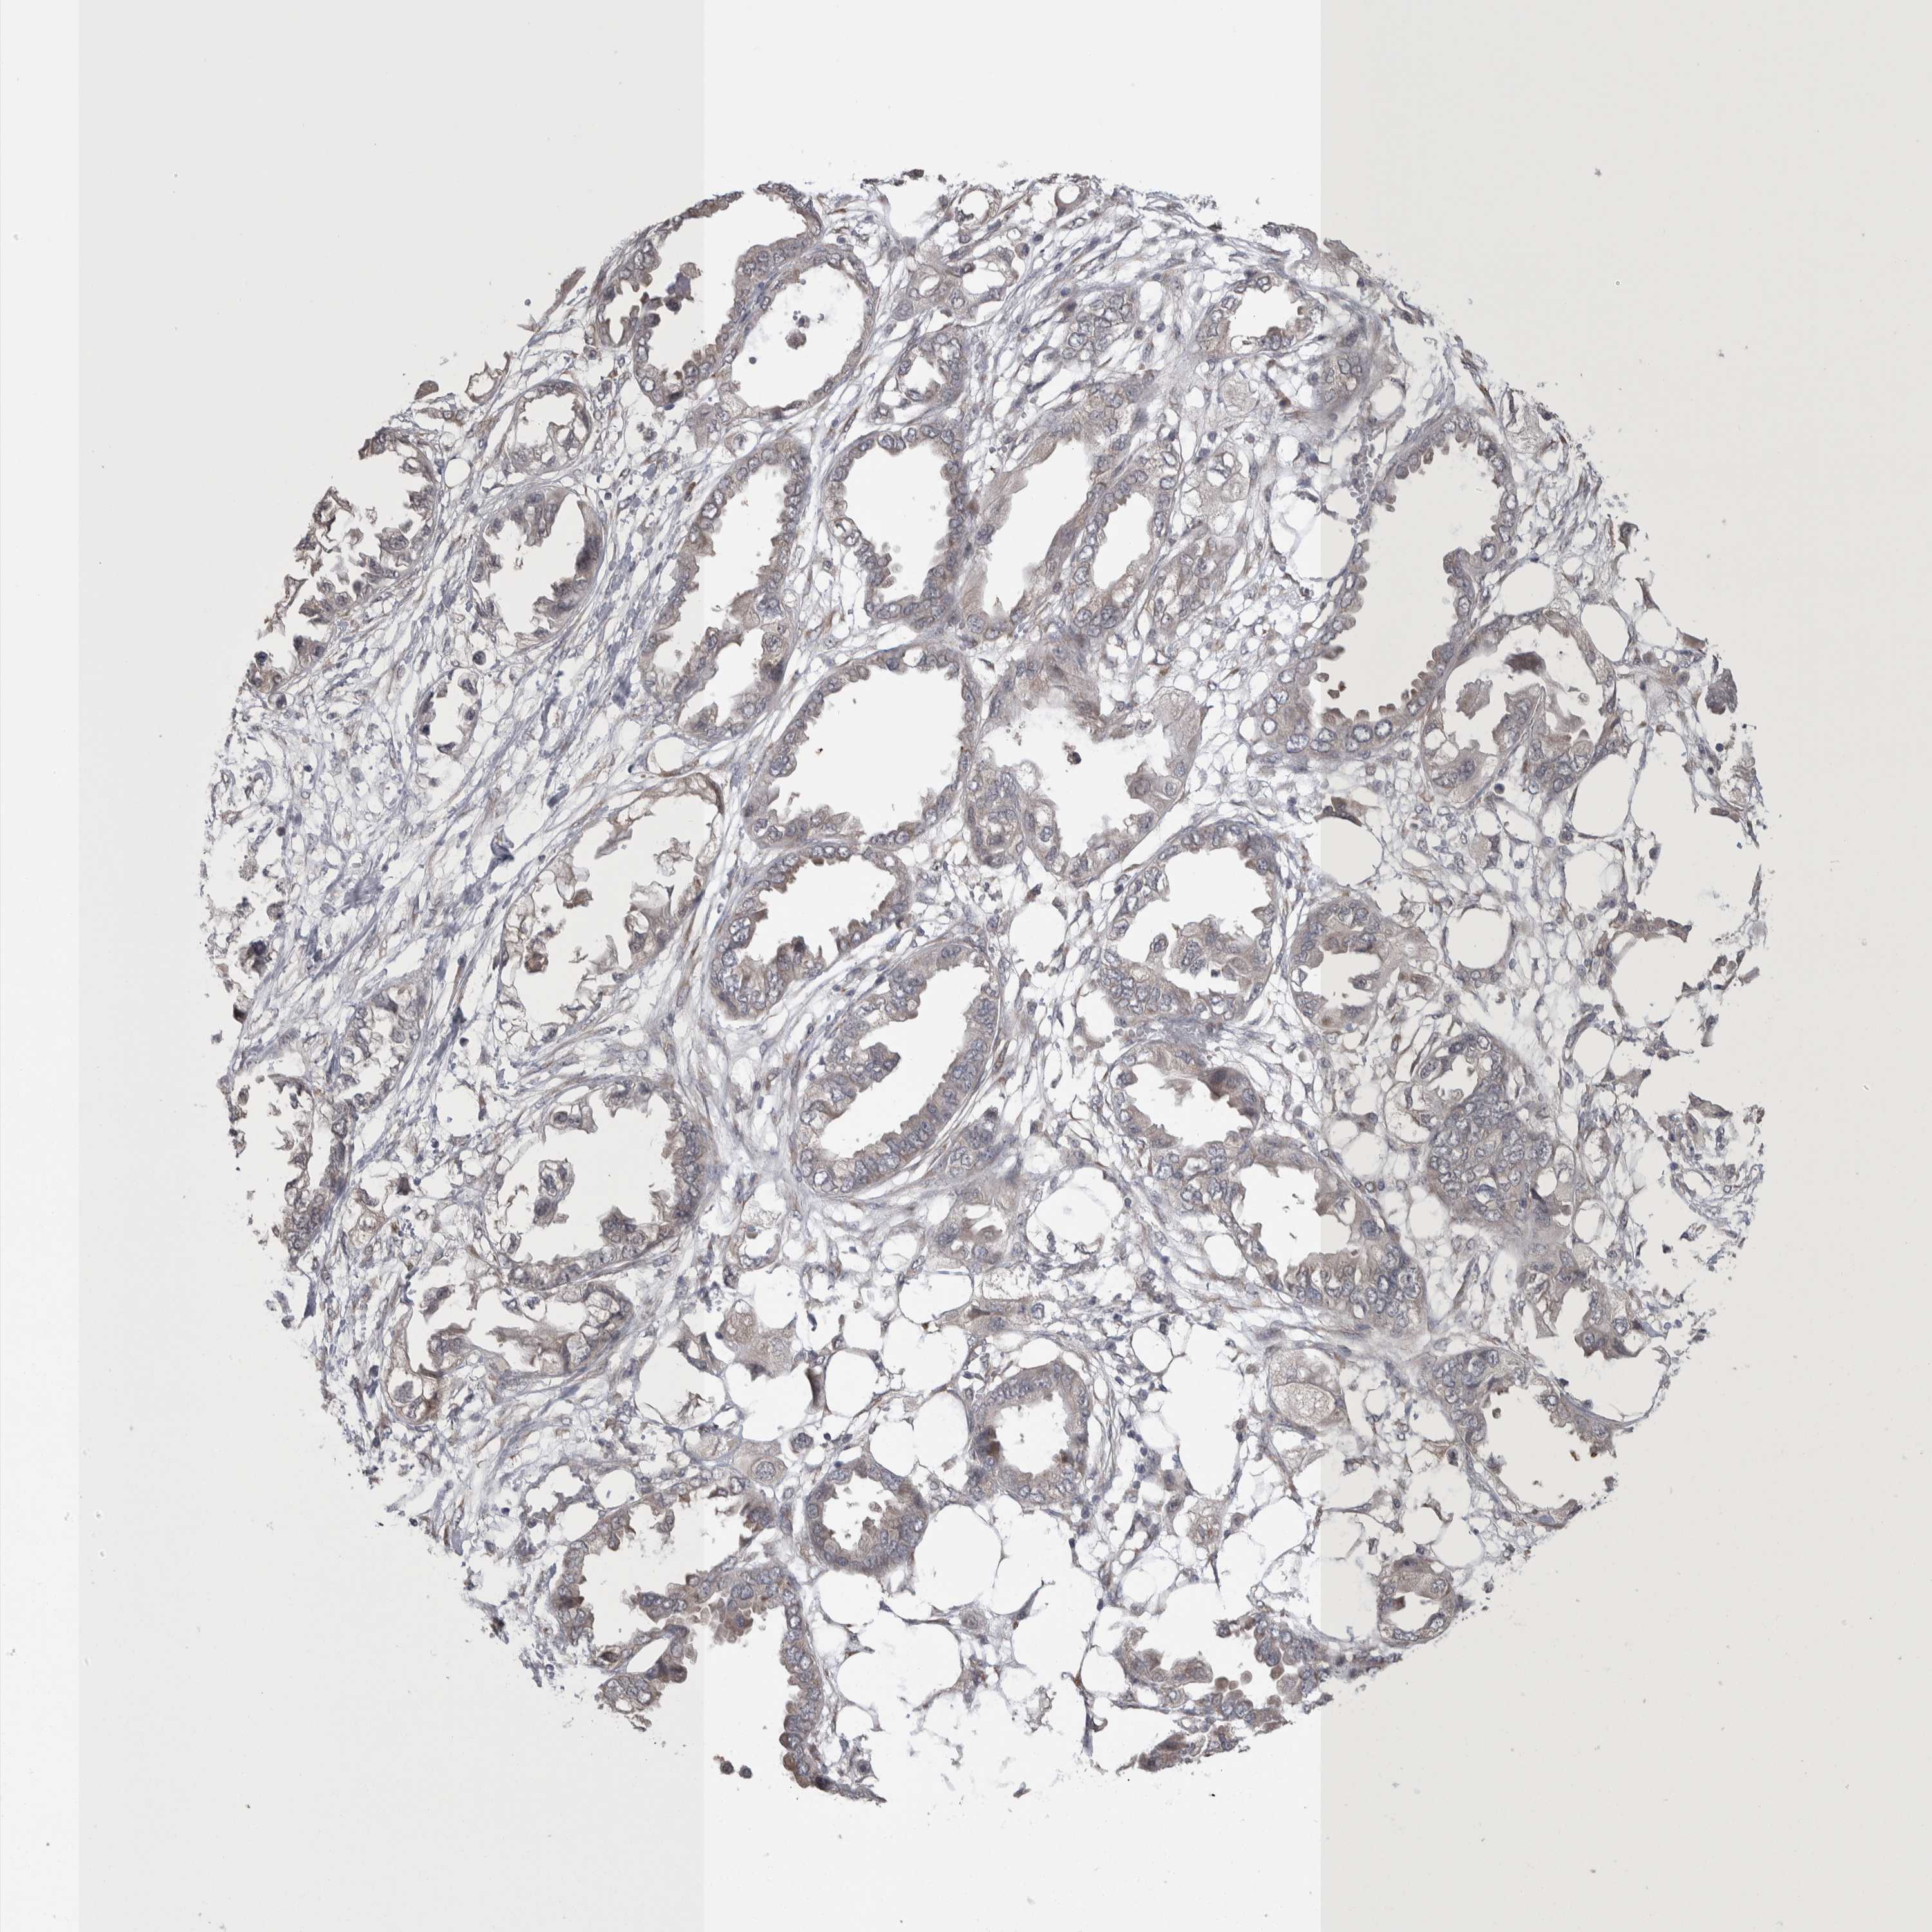

ENDOMETRIAL CANCER - Protein expressioni

A mouse-over function shows sample information and annotation data. Click on an image to view it in a full screen mode. Samples can be filtered based on level of antibody staining by selecting one or several of the following categories: high, medium, low and not detected. The assay and annotation is described here.

Note that samples used for immunohistochemistry by the Human Protein Atlas do not correspond to samples in the TCGA dataset.

Antibody stainingi

Antibody staining in the annotated cell types in the current human tissue is reported as not detected, low, medium, or high, based on conventional immunohistochemistry profiling in selected tissues. This score is based on the combination of the staining intensity and fraction of stained cells.

Each image is clickable and will lead to virtual microscopy that enables deeper exploration of all samples and also displays staining intensity scores, fraction scores and subcellular localization as well as patient and tissue information for each sample.

Antibody HPA024578

Antibody CAB002677

Staining

High

Medium

Low

Not detected

Intensity

Strong

Moderate

Weak

Negative

Quantity

>75%

75%-25%

<25%

None

Location

Nuclear

Cytoplasmic/membranous

Cytoplasmic/membranous,nuclear

Adenocarcinoma, NOS

Adenocarcinoma, metastatic, NOS

Neoplasm, malignant, NOS